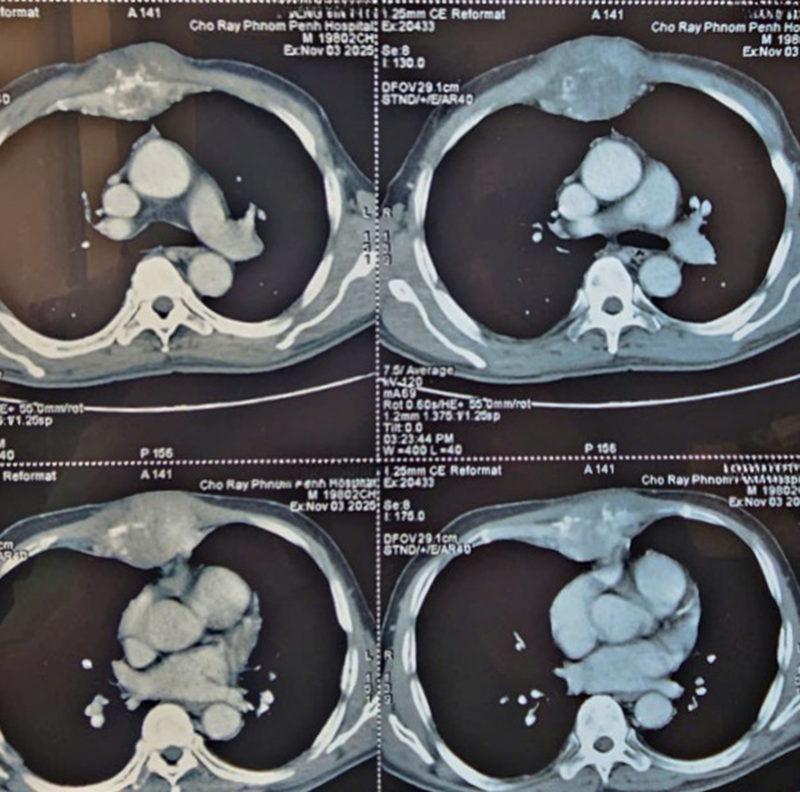

Hình ảnh chụp CT của bệnh nhân được thực hiện tại Bệnh viện Chợ Rẫy Phnom Penh

Kết quả chụp CT có tiêm thuốc cản quang cho thấy hình ảnh:

- Khối u xương ức kèm phá hủy xương, tính chất ác tính. Kích thước 6x8.8cm;

- Khối tổn thương xương sườn phải số VII và thân đốt sống L1 kèm phá hủy xương, nghi ngờ di căn xương;

- Nhiều tổn thương gan bắt thuốc cản quang, nghi ngờ di căn gan/khối u gan;

- Bờ gan không đều, gợi ý xơ gan;

- Xơ hóa và thâm nhiễm nhu mô phổi hai bên, kèm nhiều kén khí phổi.